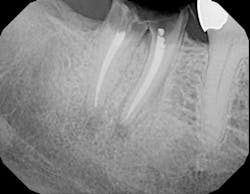

By Paul S. Rosen, DMD, MS There is a growing belief in dental practice today that if a tooth has advanced periodontal disease, it should be replaced with a dental implant rather than attempt to save it. Certainly, dental implants have been chronicled for their high level of success.1 But what if the loss of that tooth would lead to extensive restorative dentistry or the need for sophisticated procedures such as sinus elevation with concurrent bone grafting? Should the choice default to the implant or prosthetic option? Moreover, what about the patient’s desire to retain his or her own teeth? Regeneration is a treatment option for teeth with moderate to severe lesions that has demonstrated predictable success to achieve regeneration, new bone, cementum, and a functional periodontal ligament.2 Moreover, restoring these component tissues enhances the long-term survival of teeth.3 This case report documents one such instance where the loss of a premolar would have led to tremendous expenses for the patient for rehabilitation of this area.Case study This 63-year-old Caucasian female had been under routine periodontal maintenance care over the course of the last 10 years, having undergone comprehensive treatment that included surgery and rehabilitation with a fixed maxillary prosthesis. Her medical history was unremarkable except for osteopenia, for which calcium was taken. Maintenance visits were scheduled on a three-month interval and the patient was compliant with the prescribed care. Unfortunately, she experienced breakdown at the distal of the maxillary second premolar (Fig. 1) where clinical attachment loss and probing depths ranged up to 8 mm and mobility was 1+ degree. Furthermore, there was a separate but coincident periapical lesion (Fig. 2).

Fig. 1 — Pretreatment radiograph of the maxillary left second premolar. There is an advanced osseous lesion at the distal and suggestion of a developing periapical lesion.